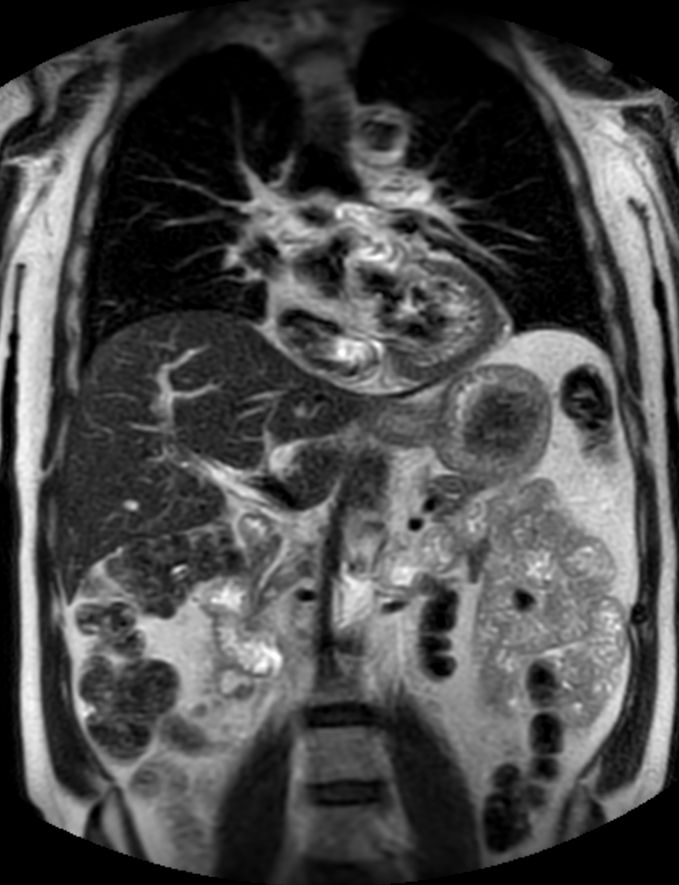

Coronal T2w TSE (2 stations)Dual coil